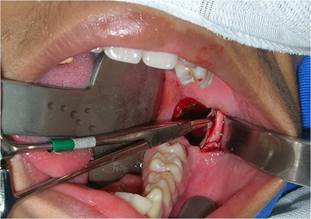

In sequence, a circumferential incision was made with a #3 scalpel handle equipped with a 15 blade, deep enough to penetrate the lesion. This tissue was removed, and a fragment of the lesion capsule was also removed separately to obtain a more specific lesion sample (Fig. 4).